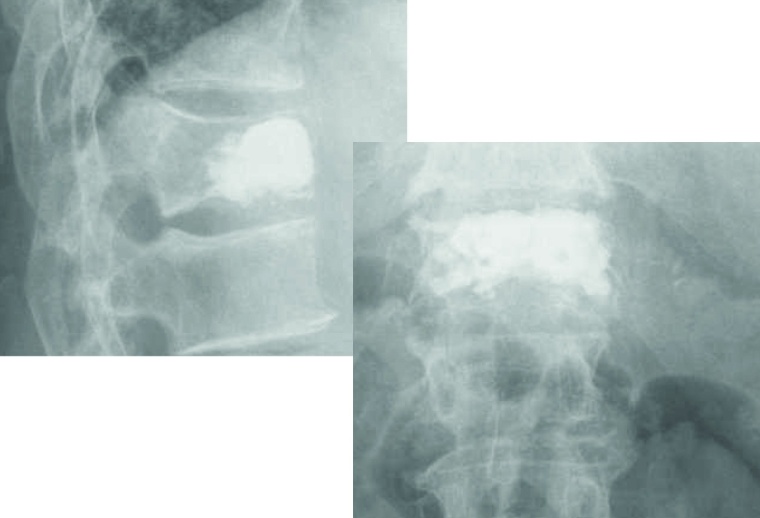

Kyphoplastie: Einfache osteolytische Metastasen können auch bei Hinterkantenbeteiligung üblicherweise bei entsprechenden Vorsichtsmaßnahmen mit der von uns bevorzugten Shieldkyphoplastie versorgt werden (Abb. 1a und b). Die reine Vertebroplastie erscheint uns in diesen Fällen zu riskant. Mit der Shieldkyphoplastie können wir die Osteolyse monopedikulär mit dem gebogenen Bohrer sehr gut adressieren und das Shield-Implantat genau dort platzieren. Perforationen im Shieldimplantat, aus denen der Zement gerichtet nach ventral austreten kann, stellen die Interdigitation mit der umliegenden Spongiosa sicher, wodurch die Stabilität erhöht wird.